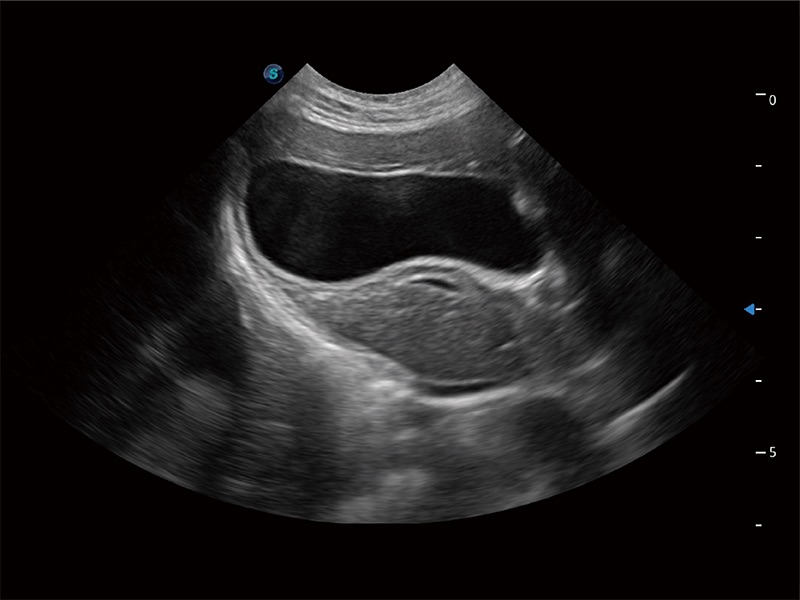

动物是人类最亲密的朋友和最值得信赖的伙伴。16877太阳集团也一直致力于探索动物专用的超声影像解决方案。全新推出的ProPet系列,是16877太阳集团在动物超声影像智能化、专业化、精准化的一次跨越式革新。动物不能用言语来表述自己的不适,通过超声影像,ProPet系列搭建了动物医生与不同物种沟通的“桥梁”,为动物医生注入了“治愈之力”。 ProPet 80 是16877太阳集团匠心打造的一款高端动物专用彩超,采用性能卓越的全新硬件架构,极大提升超声系统的运行效率和数据处理能力,帮助动物医生从容应对日益增多的挑战性病例和日益多样化的临床需求。

高性能和先进的临床应用工具可以为动物医生提供临床信心。ProPet 80 搭载了先进的腹部和浅表应用工具,帮助医生在日常临床实践中发挥前所未有的作用。

ProPet 80 专为动物医生设计,对不同的动物体型和生理结构作出了针对性的优化。通过动物影像专用软件,可满足个性化的应用需求,帮助动物医生获得更精确的诊断数据。

ProPet 80 全新的动物超声智能软件和丰富的探头群,为动物医生提供了高清晰度和精细分辨率的图像,无论在宠物、马科、畜牧还是实验室动物等应用中都可以轻松应对,为您的日常工作带来满意的体验。